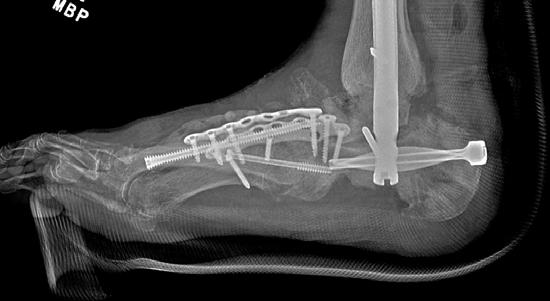

To illustrate the pitfalls of CN treatment, we have presented a 61-year-old male who already underwent midfoot fusion for prior Charcot event (Figure 2). He comes in for a second opinion and declined an ankle fusion and wanted to preserve his motion so that he could drive. The second set of radiographs demonstrate attempted hindfoot fusion that resulted in collapse to the talus bone in the ankle joint (Figure 3). Recent podiatric research shows an alternative treatment option to the traditional rigid fixation. The Charcot flipper foot construct involves fusing the hindfoot while leaving the midfoot mobile to allow for motion to lower risk of further breakdown (2). The final surgery was performed to replacing the dislocated talus with a cadaver bone and fusing the hindfoot with an intramedullary nail all through small incisions for preparation and hardware fixation. The

midfoot screws that were added in his second surgery were removed and an osteotomy was created to allow for the forefoot to move in the sagittal plane (Figure 4).

Figure 4. Final surgery resulting in plantigrade foot by fusing the entire hindfoot and unlocking the midfoot to allow for active plantarflexion of the forefoot (dotted line). The talus was replaced with a cadaver bone. Previous ulceration on the lateral ankle healed uneventfully.